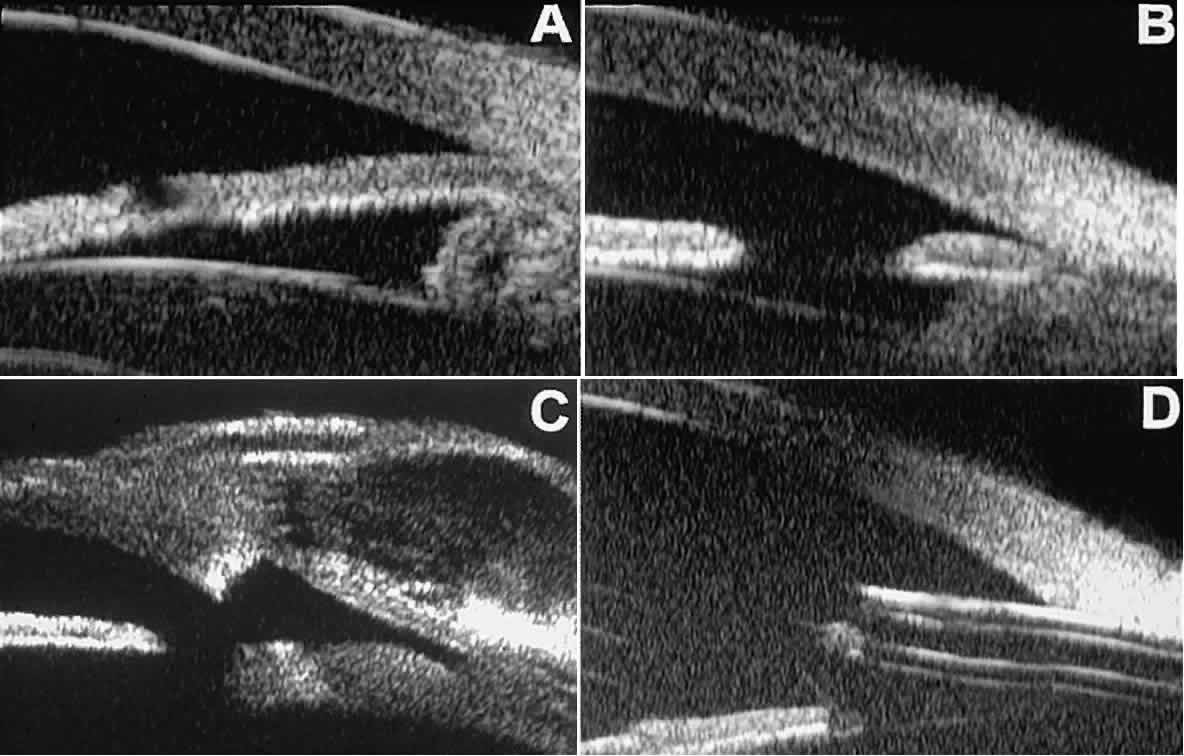

Postoperative UBM imaging of the anatomic changes caused by glaucoma surgery often helps to explain mechanisms of success and failure of the various surgical procedures (Fig. 12).3,4 After laser iridotomy, UBM can show whether the iridotomy is partial thickness (see Fig. 12A) or full thickness (see Fig. 12B) and whether the plane of curvature of the peripheral iris has changed compared with the pretreatment findings. After trabeculectomy (see Fig. 12C), UBM can show whether the scleral aperture is patent or blocked internally, whether the peripheral iridectomy is open or blocked, and whether the filtering bleb is flat, shallow, or deep.9 After tube shunt surgery (see Fig. 12D), UBM can show the position of the tip of the tube and whether its orifice is open or plugged.

Fig. 12. UBM features in glaucomatous eyes after treatment or filtering surgery. A. Incomplete peripheral iridectomy created by laser. B. Full-thickness peripheral iridectomy created by laser. C. Postoperative features of trabeculectomy including peripheral iridectomy, inner scleral defect, thin residual scleral flap, and overlying conjunctival filtering bleb. D. Tube shunt projecting radially into anterior chamber; note that the tube “shadows” deeper structures.

After any type of glaucoma filtering surgery,10 UBM can be used to detect and evaluate the extent of postoperative complications such as ciliochoroidal effusion and cyclodialysis.3,4 In ciliochoroidal effusion (Fig. 13A), UBM shows the ciliary body to be edematous and separated from the sclera by a sonolucent collection of supraciliary fluid. Many ciliochoroidal effusions that are too limited in extent to be detectable by indirect ophthalmoscopy and slit lamp biomicroscopy can be imaged by UBM. In cyclodialysis (see Fig. 13B), UBM shows a well-defined separation between the uveal tissue and the sclera in the region of the scleral spur. The width of the cleft is usually assessed best by means of limbus-concentric images through the region of interest.

Fig. 13. Complications of intraocular surgery. A. Postoperative ciliochoroidal effusion appears as slitlike spaces filled with serous fluid posterior to scleral spur. B. Postoperative cyclodialysis appears as complete separation of iris and ciliary body from sclera in region of scleral spur.